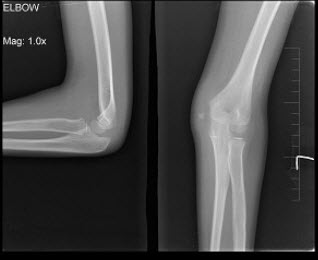

A.右髋关节结核

男,9岁,左肘外伤,结合图像,最可能的诊断为()

A.左肱骨内上髁骨骺1度分离

B.左肱骨内上髁骨骺2度分离

C.左肱骨内上髁骨骺3度分离

D.左肱骨内上髁骨骺4度分离

E.左肱骨内上髁骨骺5度分离